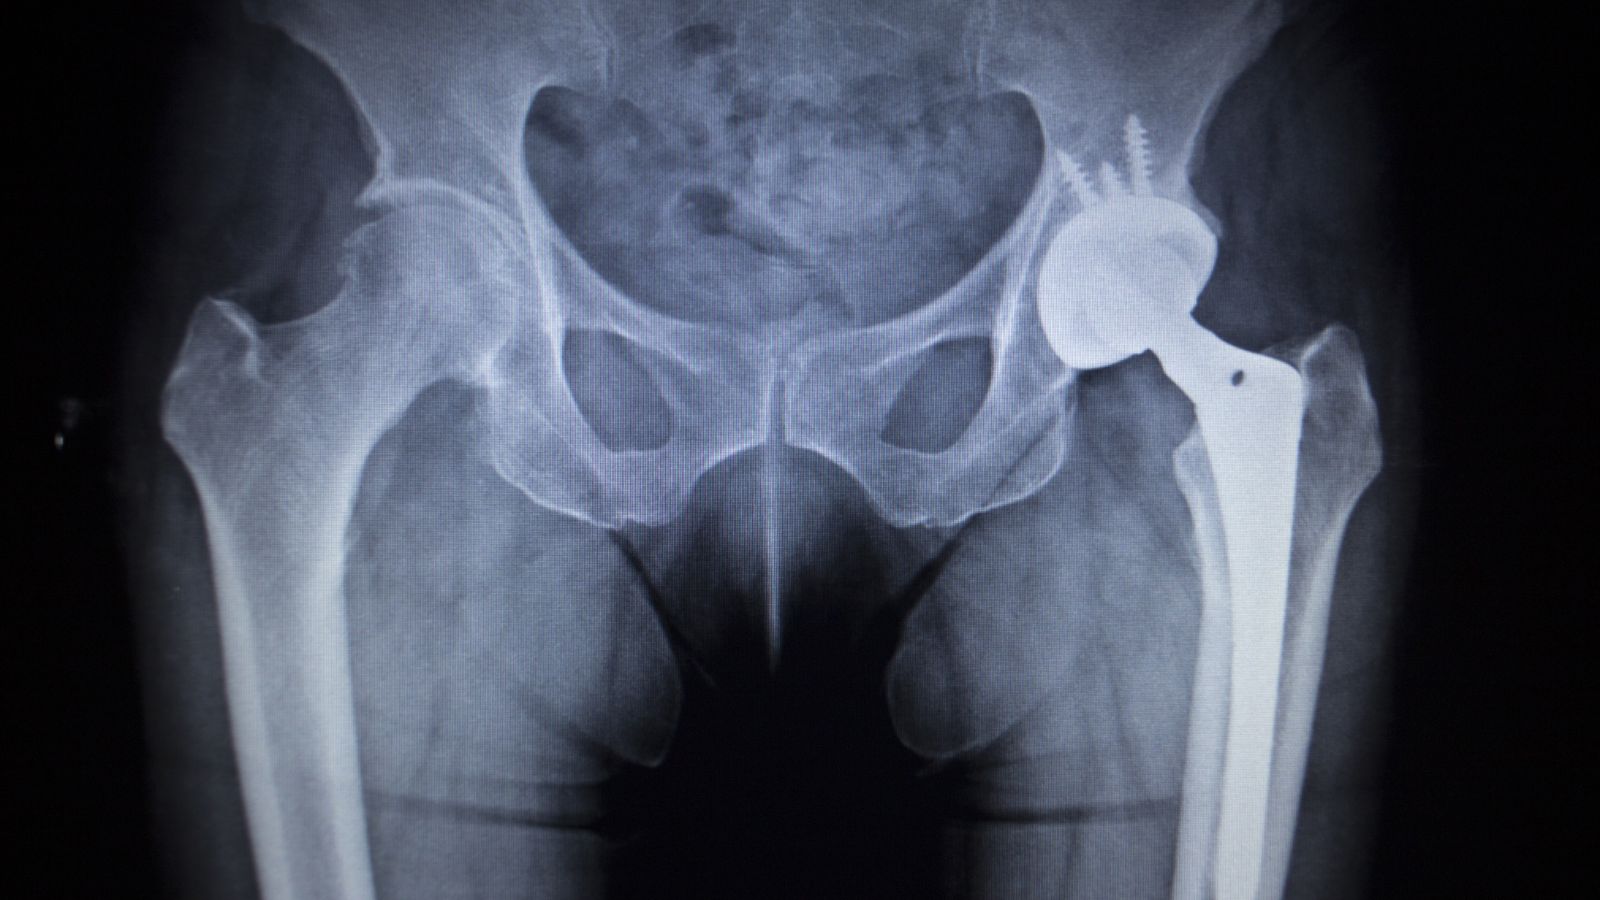

Thay khớp háng nhân tạo

Trong trường hợp hoại tử khớp háng đã gây sụp chỏm và thoái hóa nặng, thay khớp háng toàn phần là giải pháp tối ưu. Sau phẫu thuật, phần lớn bệnh nhân có thể đi lại bình thường và cải thiện chất lượng cuộc sống đáng kể.